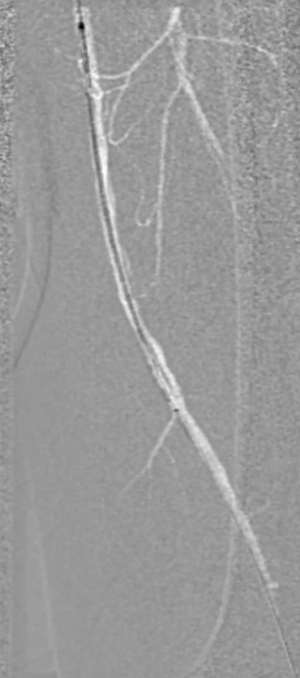

预扩张:先用3mm球囊对病变段预扩张,便于后续器械导入。

保护伞置入:于腘动脉P2段水平放入6mm Spider 保护伞,预防栓塞。

定向旋切:采用新一代Hawk-Plus定向斑块旋切装置进行减容。对于支架内闭塞段,放大图像,确保刀头在可视范围内,反复旋切至接近支架边缘;

对于支架远端病变段,分别采用4个方向各旋切1次,完成初期减容。

器械优势:刀头弧度更大,与血管壁接触面积广,切除效率更高;